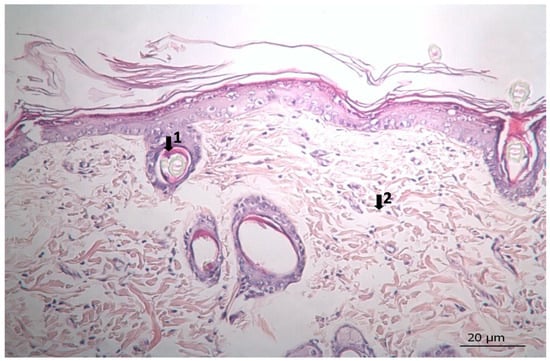

Figure 5. Histopathological view of wound healing in the placebo group (P). The skin section shows the hematoxylin and eosin stained epidermis and dermis. Arrows indicate events during wound healing: 1, fibroblast; 2, neovascularization; 3, neutrophil; 4, congestion; 5, hair follicle.

3.3. Histopathological Results

The results of histopathological observations are summarized in Table 12. Histopathological views of wound healing in the different groups are shown in Figure 4, Figure 5, Figure 6, Figure 7, and Figure 8 for C, P, M, CC, and LSC respectively. All results obtained from histopathologic observations were analyzed using the Kruskal–Wallis test for all histopathological parameters and Mann–Whitney U test for variations between two groups. Given all these results, the differences were significant in the wound healing phases of active and chronic inflammation, vascularization level, fibrosis, and fibroblastic activity. LSC was the best performing group in all favourable scores for the healing indicators.

The CC contained well-established actives such as aescin, Aloe vera, Allantoin, Calendula oil, and Hypericum perforatum extract. These herbal remedies are known for their fibroblast stimulation, anti-inflammatory, and anti-edematous effects [10,11,12,13,14,15,17,18], which translates to statistically significant improvements over C and PC groups in terms of wound contraction (Figure 3) and progressive changes in wound area measurements (Table 9 and Table 10). The results regarding full skin thickness regeneration are detailed in Table 11. The LSC group exhibited superior effects on skin thickness restoration, followed by the CC, which outperformed the P and C (control) groups, likely due to its fibroblast-stimulating constituents. Wound healing proceeds through hemostasis, inflammation, proliferation, and remodeling phases. Histopathological evaluations utilized cellular markers to delineate these stages: neutrophils and mononuclear cells as indicators of inflammation [56], while the recovery phase of wound healing is marked by fibrosis and hair follicle formation, decreased neovascularization, and disappearance of neutrophils and mononuclear cells [56,57,58]. In histopathological investigations of this study, neutrophils and mononuclear cells are used as indicators of the inflammation phase [56]. Histopathological views presented in Figure 4, Figure 5, Figure 6, Figure 7 and Figure 8 and a summary of results of the seen histopathological indicators (Table 12) showed minimal active inflammation, evidenced by low neutrophil presence across all groups. Chronic inflammation, defined by mononuclear cell infiltration [50,59,60], was absent in the LSC and CC groups but notable in the C and PC groups (Table 12), which underscored the anti-inflammatory properties of active ingredients. On the other hand, the proliferation phase is assessed by fibroblastic activity and neovascularization [56,57,58]. Fibroblast activity, critical for collagen synthesis and extracellular matrix production {5}, was also highest in the LSC group, aligning with its enhanced healing capacity. Neovascularization, essential for oxygenation and nutrient supply during new tissue formation [61,62] was significantly improved in LSC and CC groups compared with the other groups, supporting the multifaceted roles of the active contents in accelerating wound healing (Table 12). Fibrosis, defined as excessive collagen deposition leading to scar formation, was reduced in P and LSC groups, indicating less aberrant repair [60,63,64], and hair follicle neogenesis, which is an important parameter of advanced healing and regeneration and correlates with remodeling [60,64,65,66]. This was most pronounced in the LSC-treated wounds (Table 12, Figure 8). At the designated time point (day 9), wounds treated with LSC and CC had transitioned into the remodeling phase, while C- and PC-treated wounds remained in the proliferation phase. The M group was nearing remodeling (Figure 6). Collectively, these findings substantiate the superior wound healing efficacy of LSC and CC relative to others used as controls and comparisons.